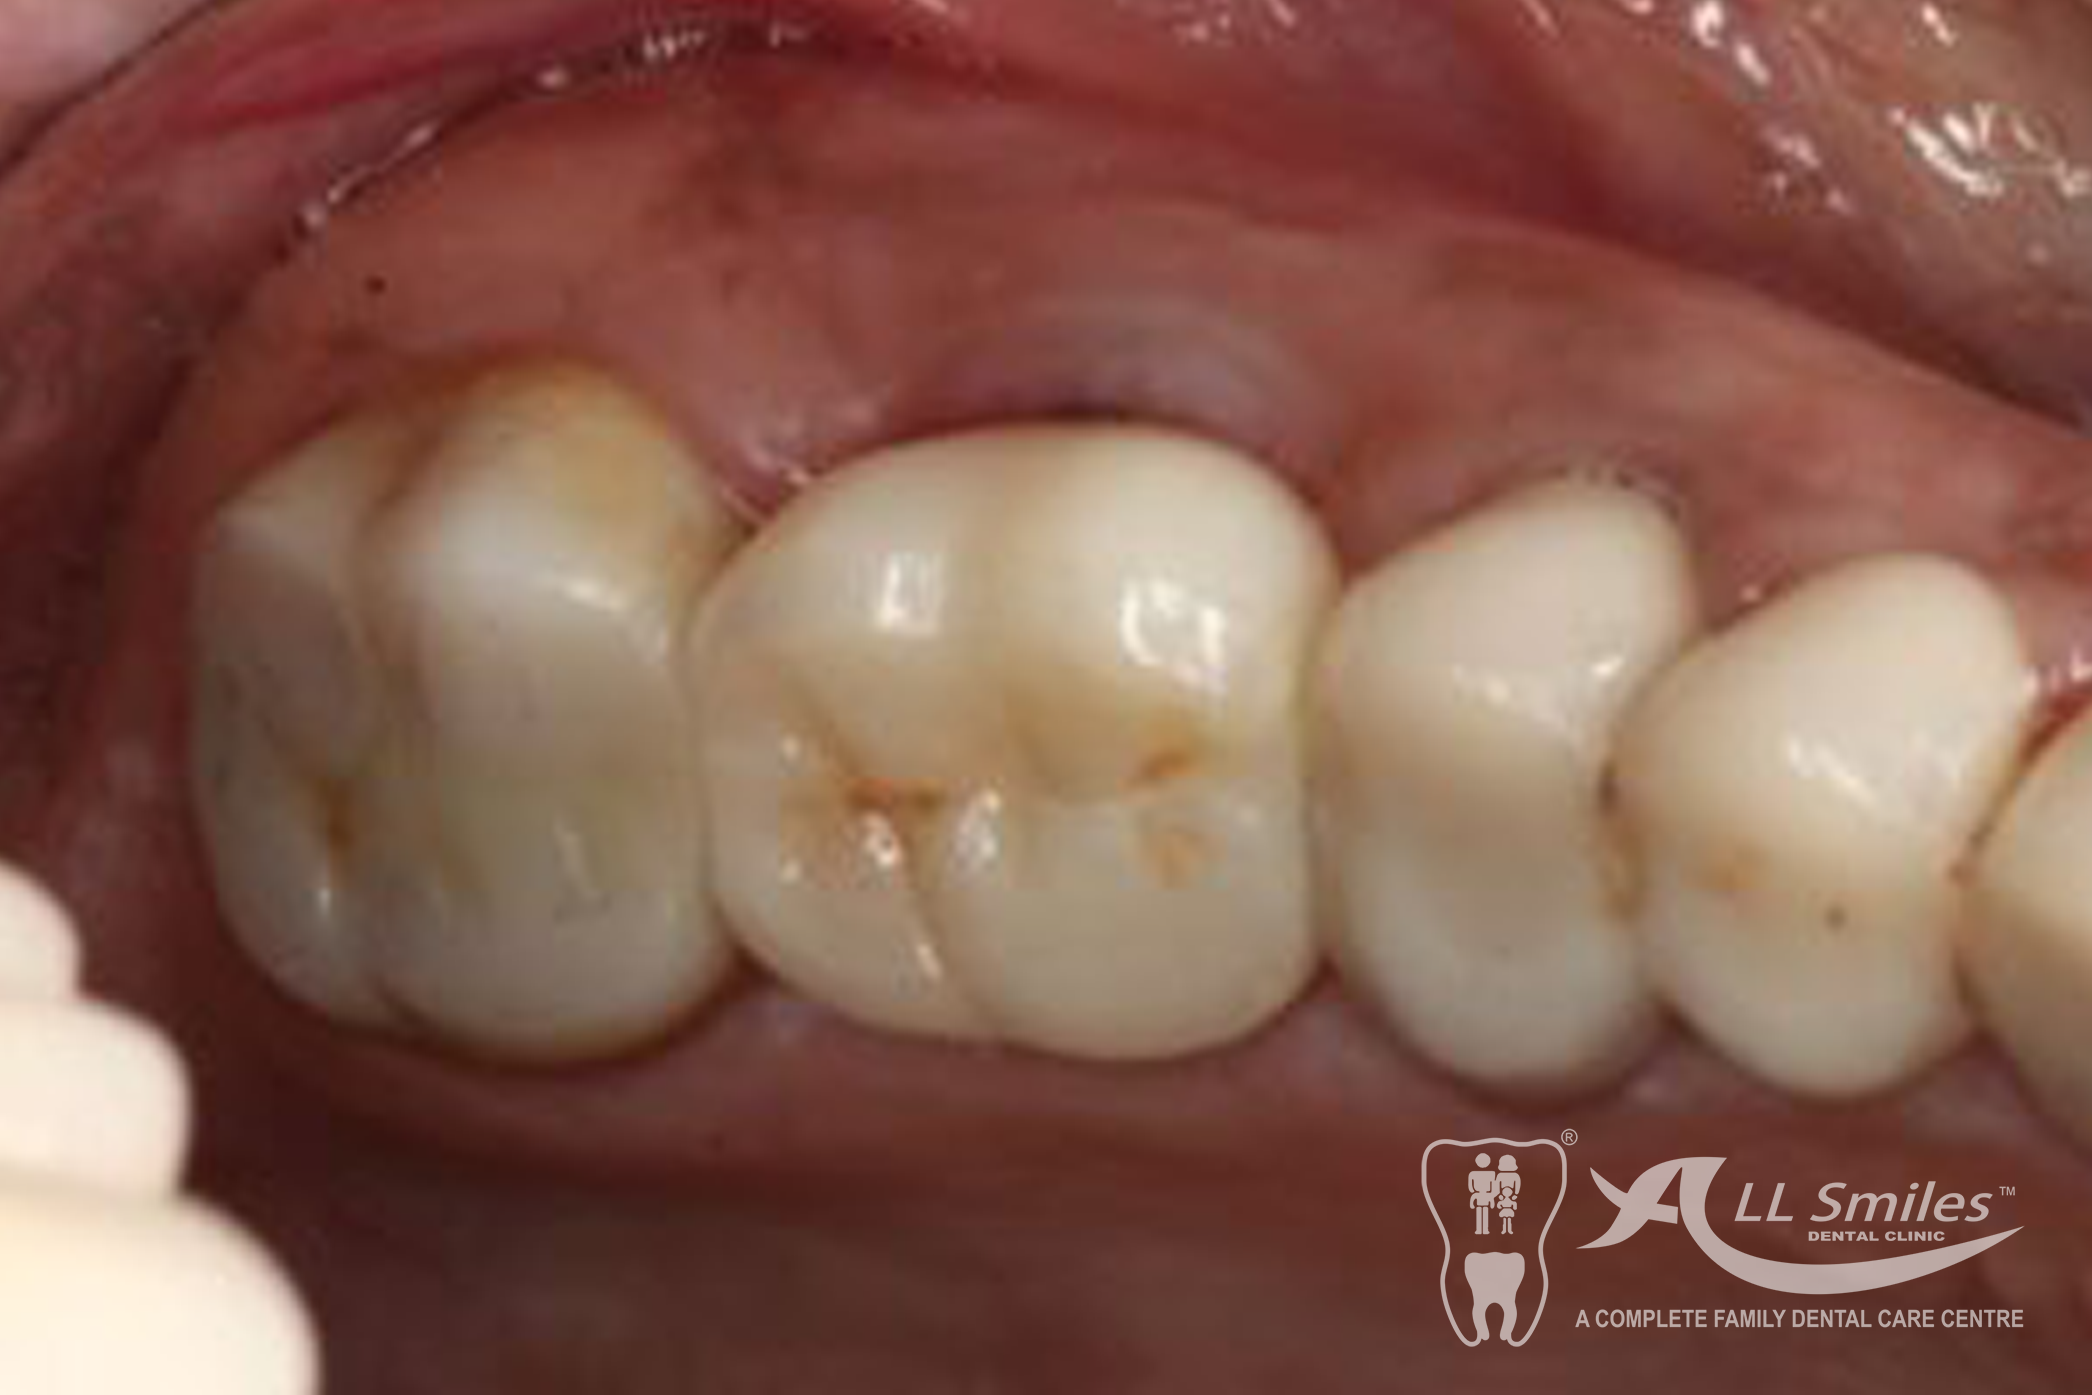

Dental Implants Gallery